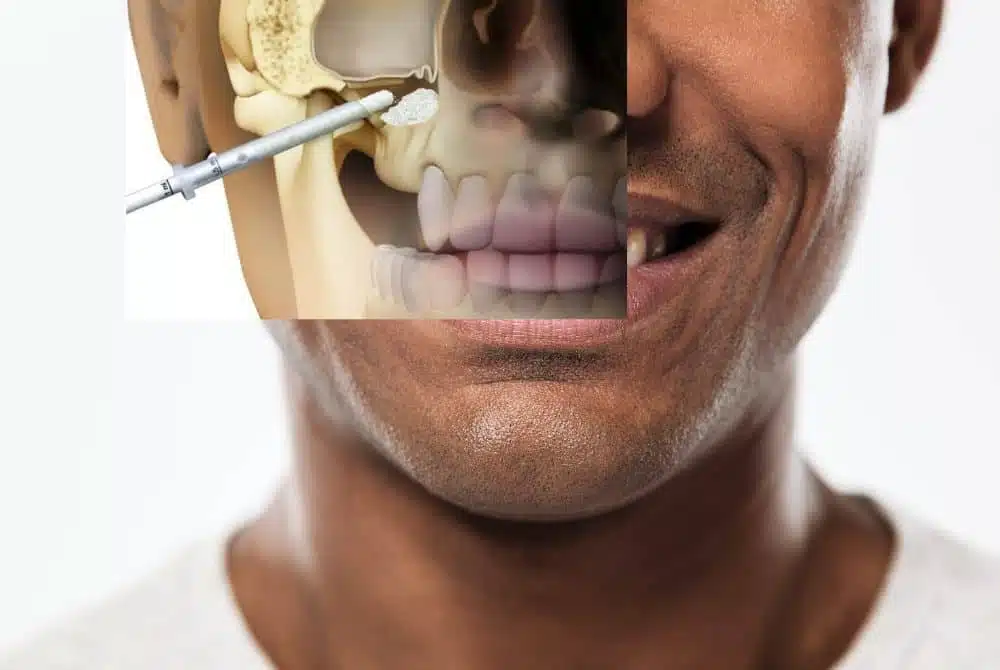

Kemik Grefti ve Sinüs Lifting

İmplant tedavisi öncesinde yetersiz kemik hacminin artırılmasına yönelik cerrahi uygulamalardır. Kemik desteğinin sağlanması amacıyla planlanmaktadır.

Tedavi öncesinde detaylı klinik muayene ve üç boyutlu görüntüleme (CBCT) değerlendirmesi yapılır. Çene kemiğinin hacmi, yoğunluğu ve anatomik yapılar analiz edilerek implant planlaması oluşturulur. Hastanın sistemik hastalıkları, kullandığı ilaçlar ve sigara alışkanlığı gibi faktörler de değerlendirme sürecinin önemli bir parçasıdır.

Ağız hijyeninin iyi olması ve varsa mevcut enfeksiyonların tedavi edilmesi gerekir. Planlama aşamasında dijital ölçü ve simülasyonlar kullanılarak hem fonksiyonel hem estetik beklentiler göz önünde bulundurulur. Bu hazırlık süreci, cerrahi aşamanın daha kontrollü ilerlemesine katkı sağlar.

İmplantların kemikle biyolojik olarak kaynaşma süreci (osseointegrasyon) birkaç ay sürebilir. Bu dönemde düzenli kontroller önemlidir. Nihai protez aşamasına geçmeden önce iyileşme süreci klinik ve radyolojik olarak değerlendirilir.